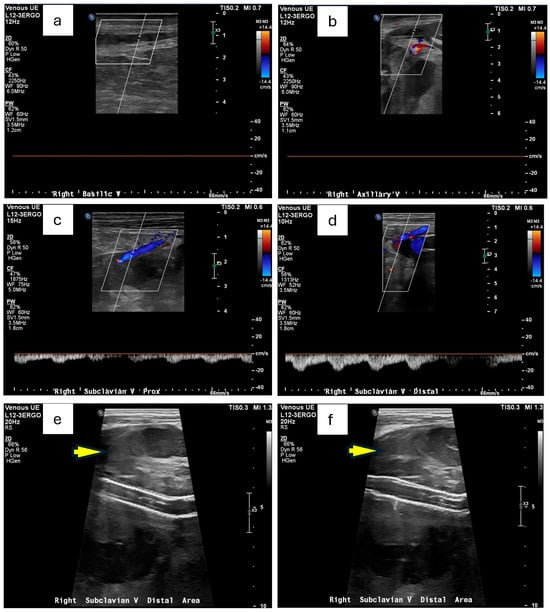

On hospital day 4 (3 days after endovascular repair of the left subclavian artery aneurysm), a repeat CT scan (Figure 3) was performed. Axial chest images (Figure 3a) showed a trace right pneumothorax (yellow arrow), unchanged since the day of admission. Sequential axial views (Figure 3b,c) demonstrated the right axillary hematoma, stable in size since hospital day 2 and without imaging findings suggestive of superinfection. Finally, an axial view of the proximal right subclavian artery (Figure 3d) revealed a type 1A endoleak in the right subclavian artery stent, indicating a possible proximal seal failure or ongoing infection that prevented full exclusion of the aneurysm (as pointed by the yellow arrow in Figure 3d). Although the patient’s white blood cell count gradually improved, and follow-up blood cultures eventually turned negative on hospital day 4 (as shown in Table 1), the possibility of a mycotic stent graft persisted. Vascular Surgery concluded that definitive source control might necessitate surgical graft explanation with extensive debridement, a high-risk procedure best conducted in a tertiary or quaternary center.

Figure 3. CTA on hospital day 4, 3 days after endovascular repair of the left subclavian artery aneurysm). (a) Axial chest CTA shows a trace right pneumothorax (yellow arrow), unchanged since the day of admission. (b,c) Sequential axial views demonstrating the right axillary hematoma, which remains stable in size since hospital day 2, without imaging findings suggestive of superinfection. (d) Axial view of the proximal right subclavian artery reveals residual but diminished aneurysmal filling around the stent graft (pointed by the yellow arrow), representing improvement compared with earlier imaging on the day of admission.